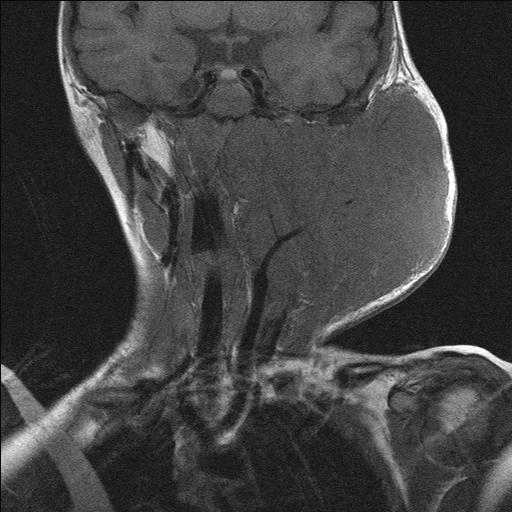

Only 4 % of liposarcomas are found in the head and neck region, yet liposarcoma is the most common soft tissue sarcoma in the maxillofacial region. The neck is the most common site, the lesion usually presents as a soft lump. The second most common site is the scalp. Liposarcomas in the head and neck region (see Figure 1) are thought to be significantly more often low-grade (less aggressive) malignancies than liposarcomas of other parts of the body. Simple excision and reconstruction has a reasonable high success rate.

Figure 1: Liposarcoma of the tongue.